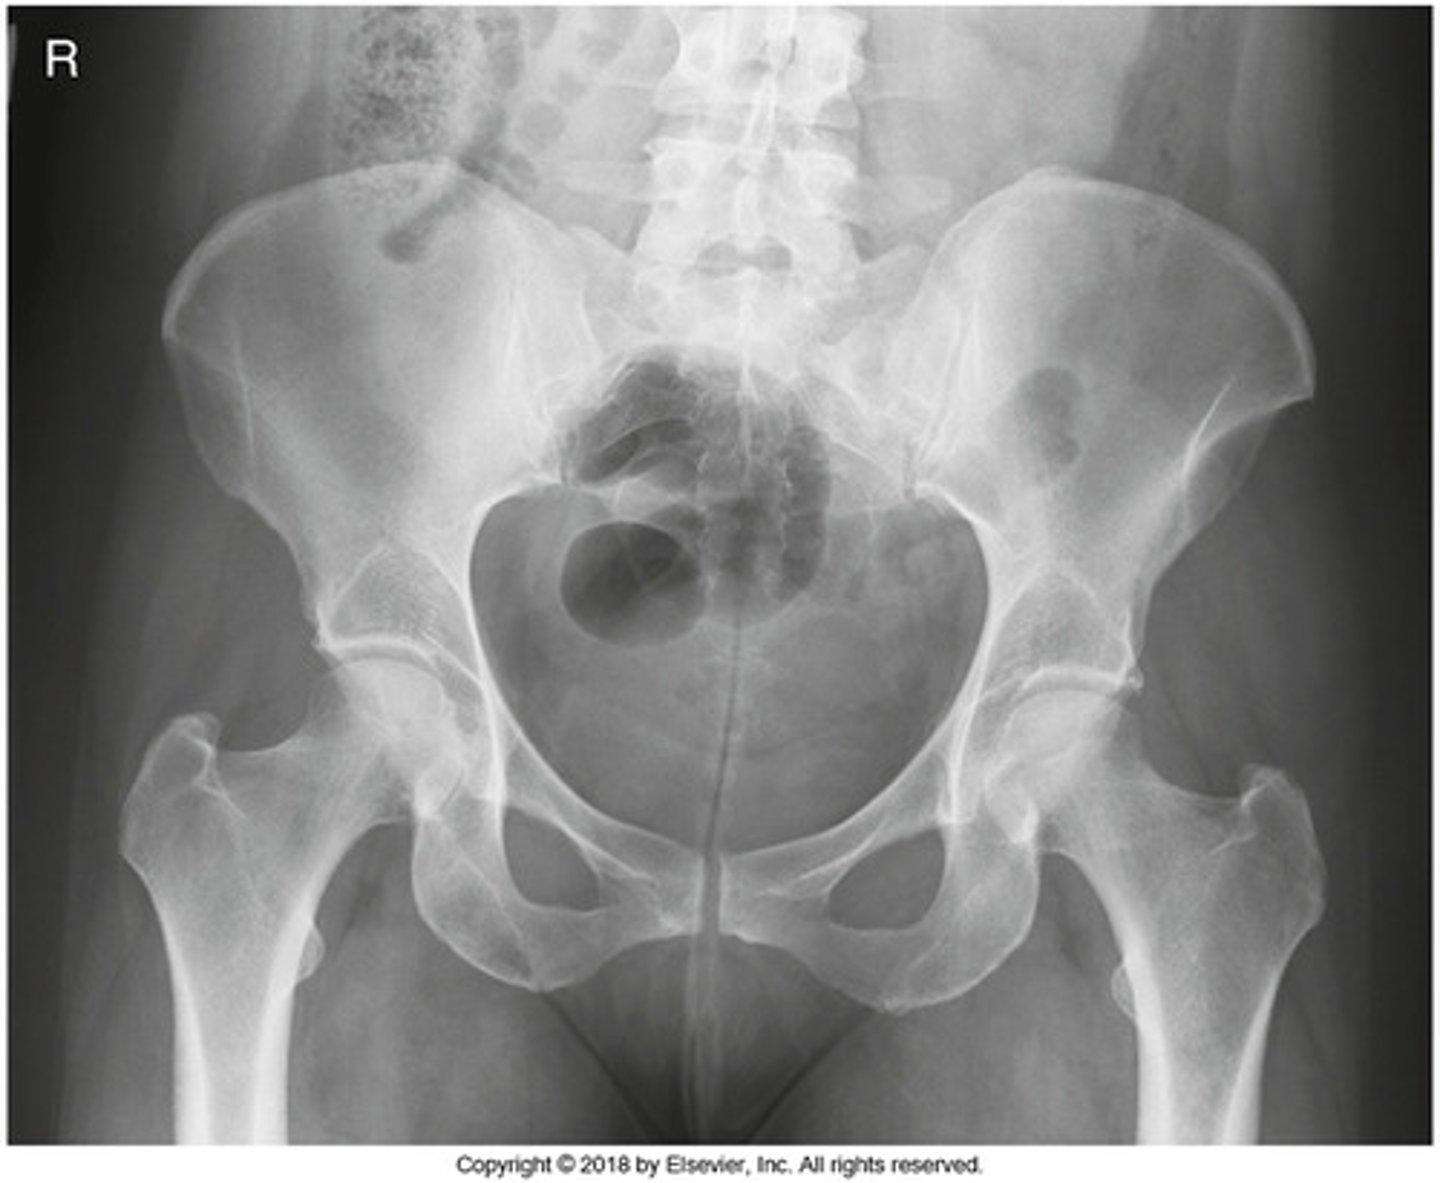

Identify the projection:

AP hip

AP oblique hip

AP pelvis

Lateral hip

IA Positioning: AP Pelvis

- leg internally rotated (15-20 degrees)

- femoral neck not foreshortened

- only a small amount of lesser trochanter visible beyond medial border

- greater trochanter in profile

- crests on same level and symmetrical

- symmetrical obturator foramen

- ischial spine seen/not seen (equally on both sides)

- sacrum and coccyx aligned to PS